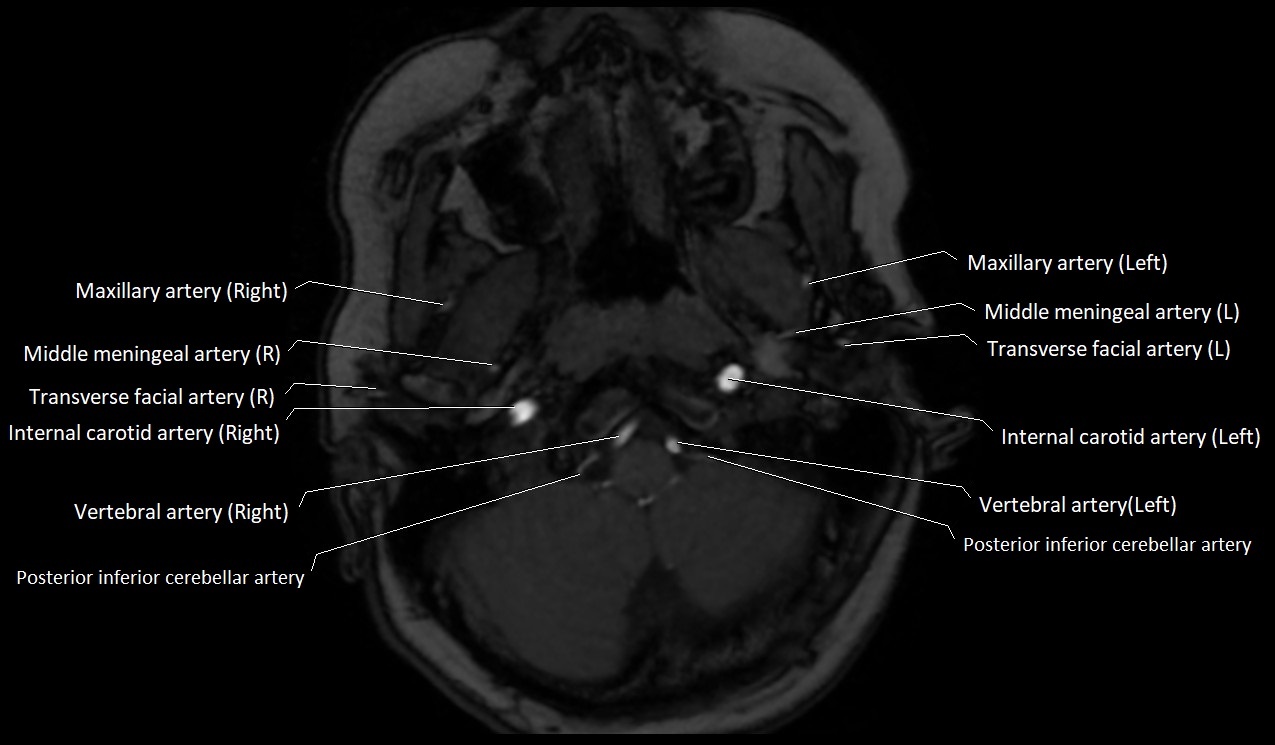

CT image

image